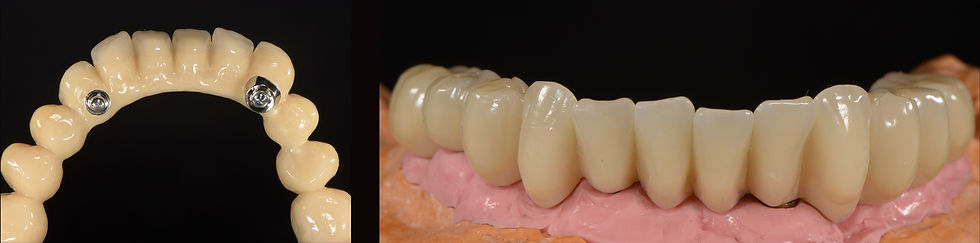

Occlusal view of the lower Toronto Bridge: screw passages are in favourable prosthetic positions

Vision of the interrelationships between jaws: the II prosthetic class was brought to the I class in the cusp-fossa so that no movements of the upper prosthesis were generated

Details of the lower Toronto bridge